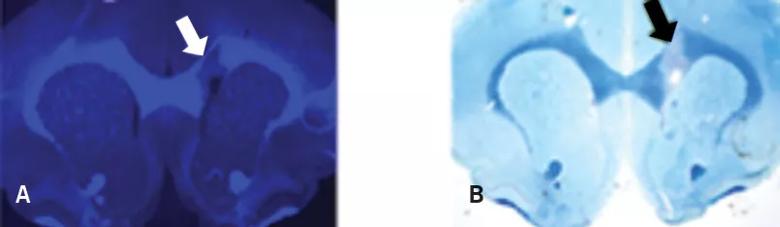

To assess its translational potential for use in humans, Myelivid underwent extensive preclinical testing.1,2 This included tests in experimental systems to demonstrate that the molecule specifically detected myelin in normal brain tissue and could sensitively demonstrate abnormal myelin changes as well (Figure 2).

Myelivid stains normal myelin and sensitively detects myelin lesions

Figure 2. Myelivid stains normal myelin and sensitively detects myelin lesions. Brain tissue specimens from a murine model were stained with Myelivid (A) and Luxol fast blue stain (B) and visualized with fluorescence microscopy (A) and light microscopy (B). The bright signal in panel A is due to intrinsic fluorescence properties of Myelivid. Stains were performed on adjacent slices of brain tissue obtained from the same subject. Arrows indicate the site of a myelin lesion, which is conspicuous due to decreased uptake of Myelivid and Luxol fast blue stain.